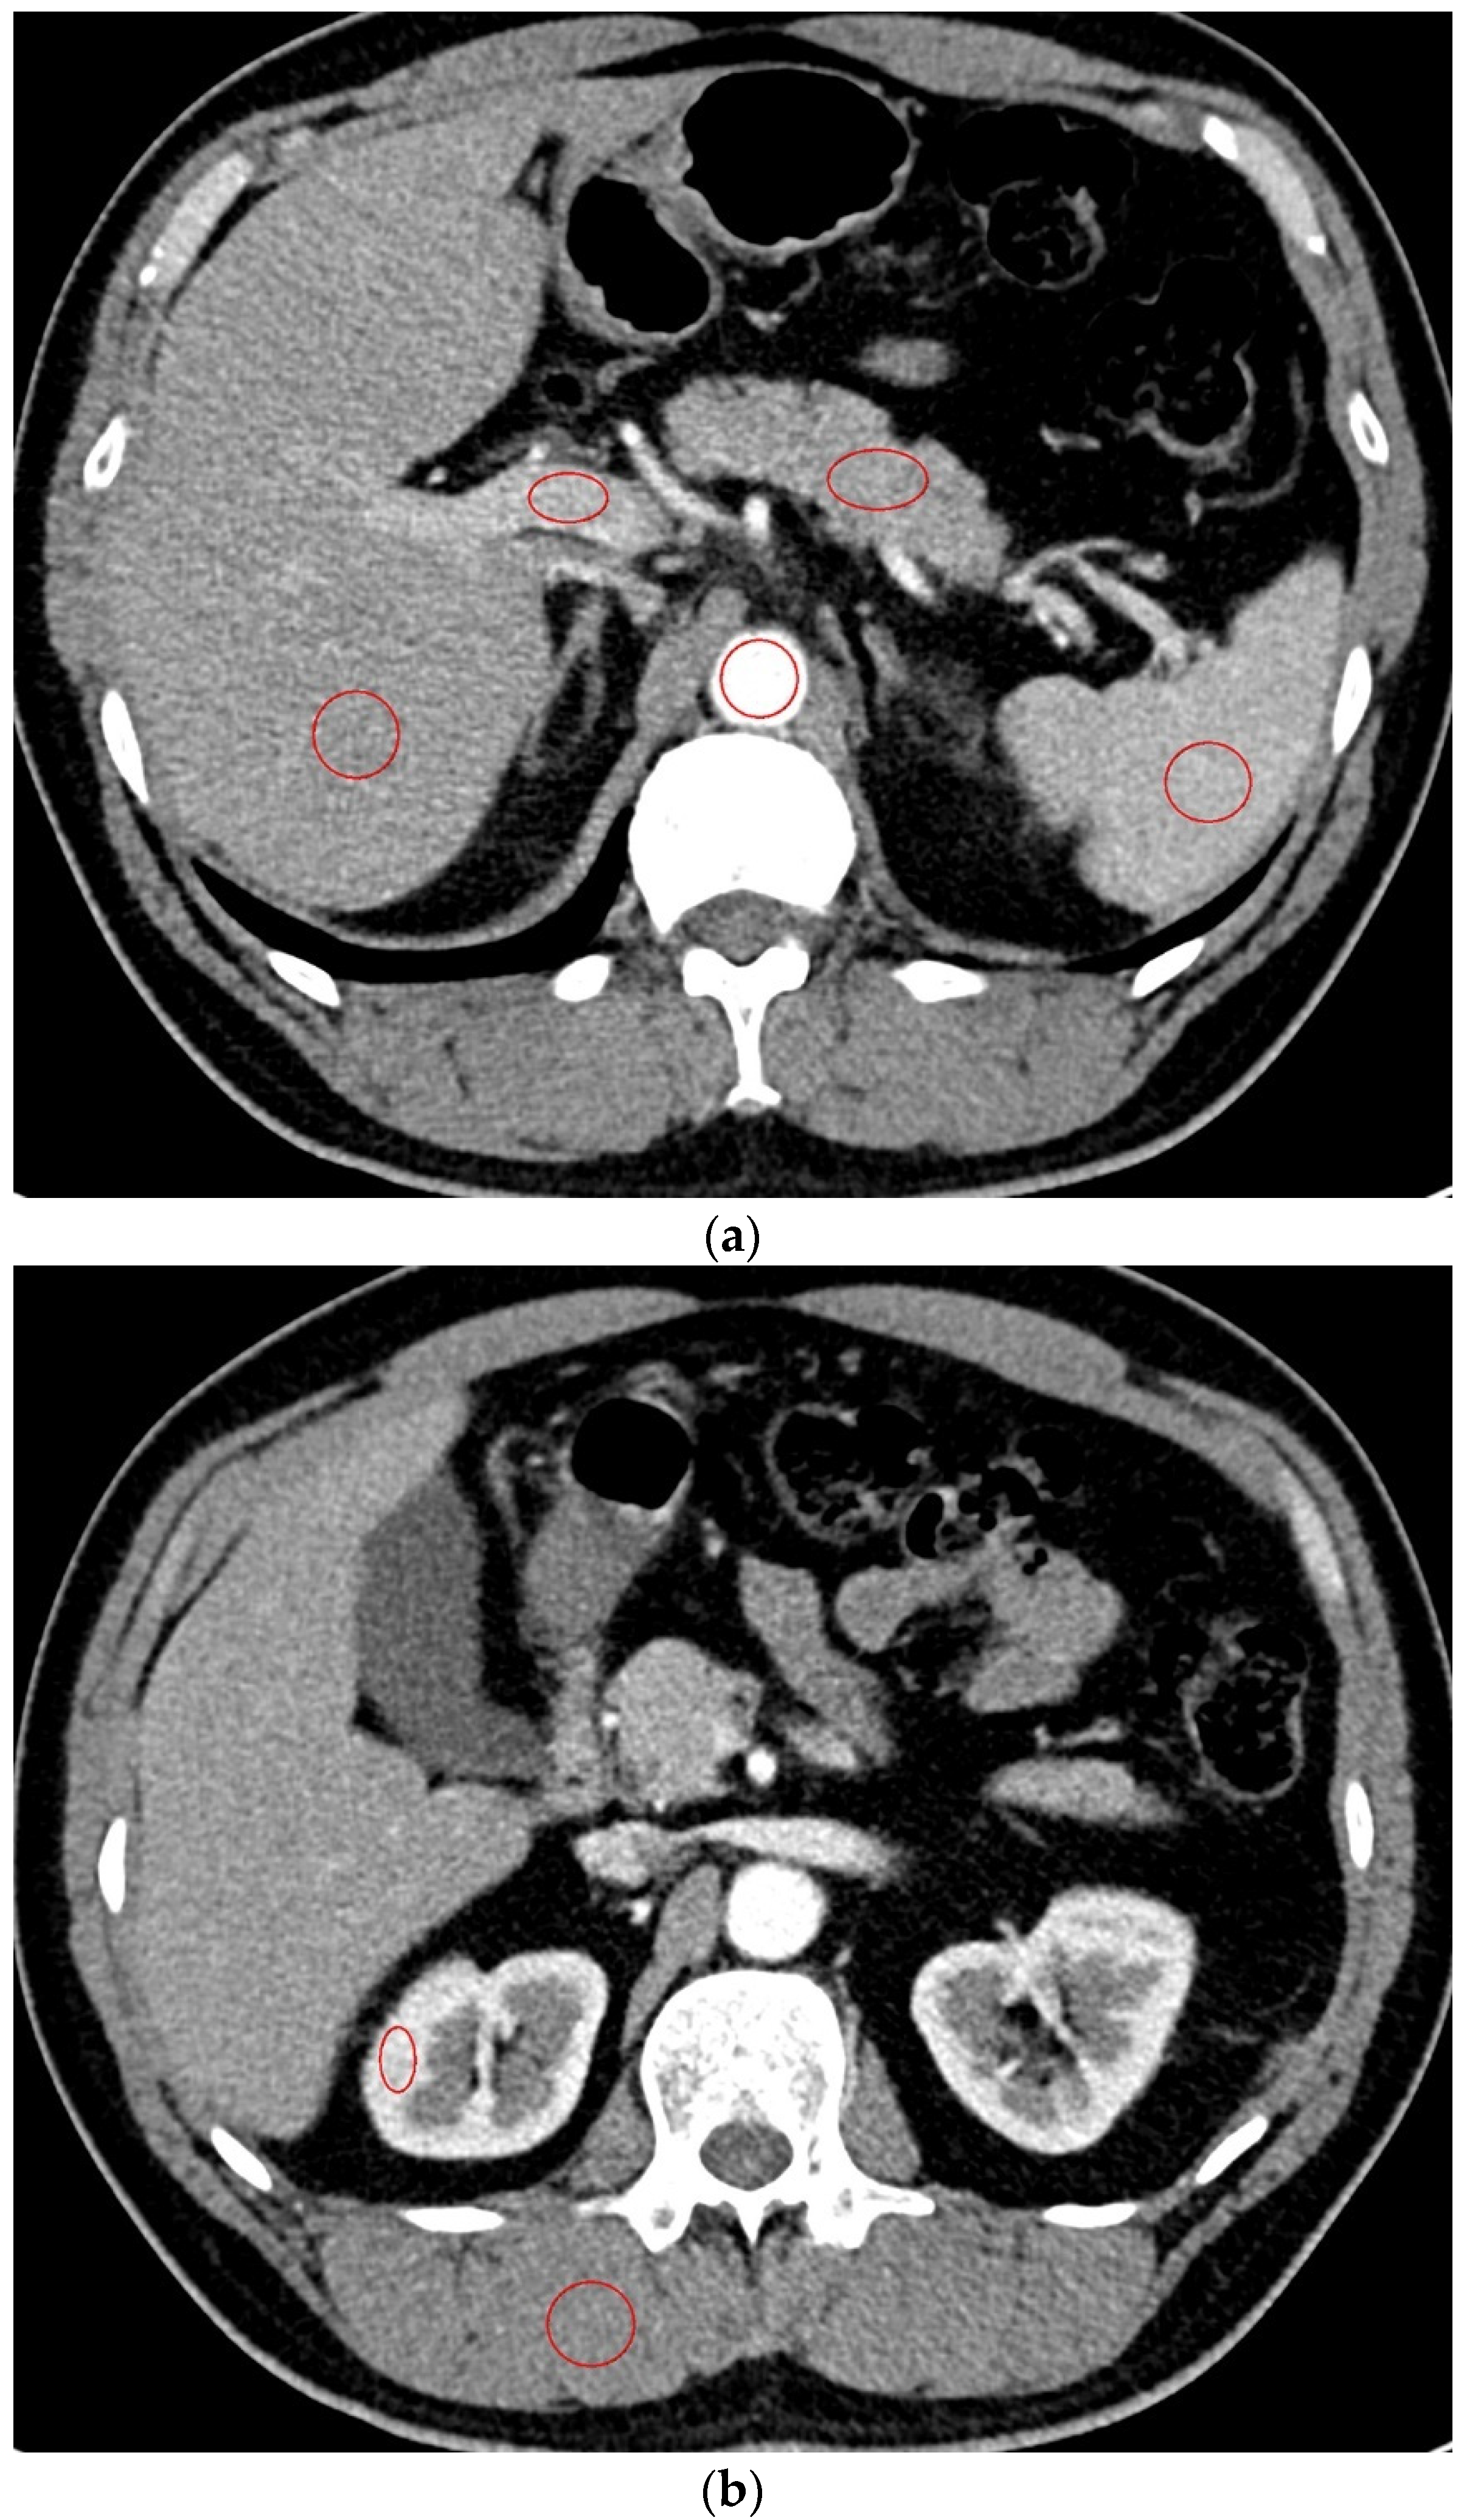

A total of 212 focal hepatic lesions, including 134 cysts, 25 hemangiomas, and 53 malignant lesions, were detected in all the examinations. The interreader agreement was fair to excellent for three diagnoses. The Kappa values between the two radiologists to detect cyst, hemangioma, and malignancy were 0.802, 0.712, and 0.935 in all the examinations, 0.796, 0.808, and 0.905 in Group A and 0.808, 0.610, and 0.923 in Group B. Compared to the gold standard, sensitivity was lowest for the hemangiomas by both readers in Group B (Table 6). Sensitivity to detect cysts was lower by reader 1 and higher by reader 2 in Group A than in Group B. Specificity was higher than 98% for three diagnoses by both readers. CT images of the representative patient who underwent CT scans using two different CMs are shown in Figure 3.

Figure 3. A 64-year-old female patient who underwent CT examinations using the same machine (machine B). An approximately 0.7-cm cyst is noted in liver segment 8 on both CT examinations with 240 mgI/mL contrast material (a) and 320 mgI/mL contrast material (b).